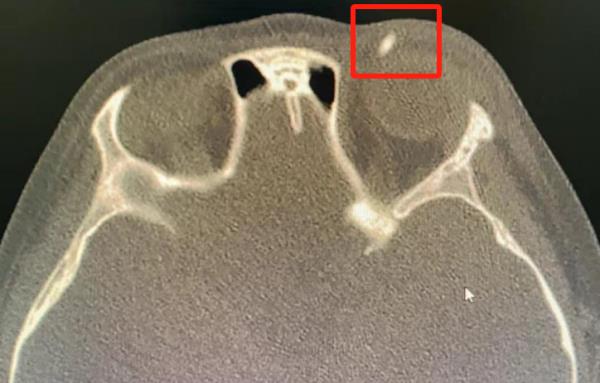

眼科医生详细查体后怀疑,可能有异物存留,于是针对性地为孩子开具了眼眶CT,结果提示:苗苗的眼睑内果然存有异物。眼科医生判断,这可能是一根断掉的铅笔芯!

图源:青岛市妇女儿童医院

眼科医生紧急给孩子安排手术,在局麻下取出异物,果然是一根长约半厘米的铅笔芯。苗苗的妈妈心有余悸,本以为是简单的伤口感染,没想到里面竟残留了异物!